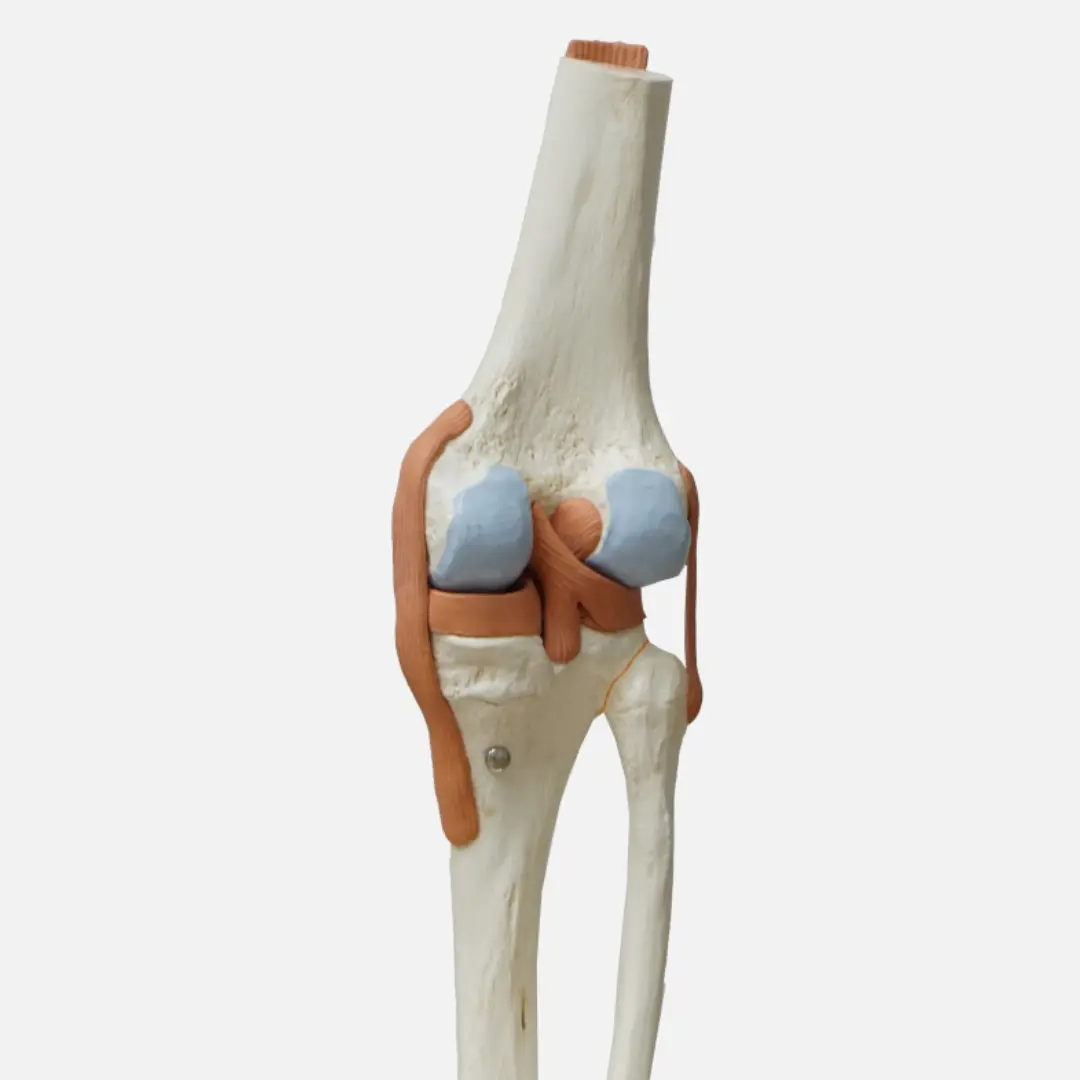

글루코사민(Glucosamine)은 우리 몸에서 자연적으로 생성되는 아미노당의 일종이에요. 주로 연골, 인대, 힘줄, 피부 등 결합 조직에 풍부하게 존재하며, 특히 관절 연골의 주요 구성 성분인 프로테오글리칸(Proteoglycan)과 히알루론산(Hyaluronic acid)의 중요한 재료가 됩니다.

연골은 관절에서 뼈와 뼈가 직접 부딪히는 것을 막아주고, 충격을 흡수하며, 부드러운 움직임을 가능하게 하는 쿠션 역할을 합니다. 이 연골은 콘드로이틴과 함께 글루코사민을 통해 건강하게 유지될 수 있어요. 하지만 나이가 들거나, 과체중, 과도한 운동 등으로 인해 연골이 손상되거나 글루코사민 생성 능력이 떨어지면 연골이 닳아 없어지고 탄력을 잃게 됩니다. 이는 결국 관절 통증과 염증을 유발하는 퇴행성 관절염으로 이어질 수 있어요.